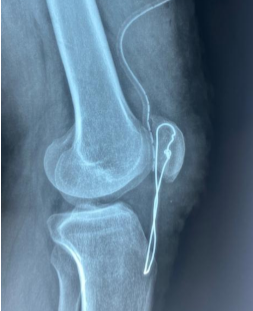

Neglected Ruptures of the Patellar Tendon: Report of Three Cases in the Orthopedic Trauma Department of Dalal Jamm Hospital, Dakar

Malick Diop , Mayoro Sow , Badara Dembele , Mohamed Daffé , Badara Diop , André D Sané

………………………………p.258-262